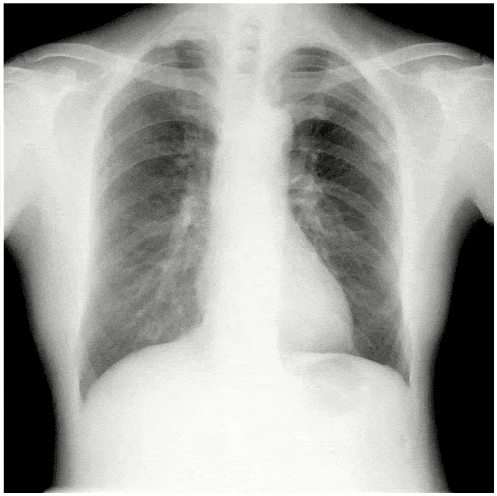

デジタルX線動画撮影システム(Dynamic Digital Radiography)は従来の単純X線撮影と同様に、一般X線撮影装置を用いて簡便に撮影できる新たな検査法であり、回診用X線撮影装置「AeroDR TX m01」によりベッドサイドでのX線動画撮影が可能となり、更なる広がりを見せています。